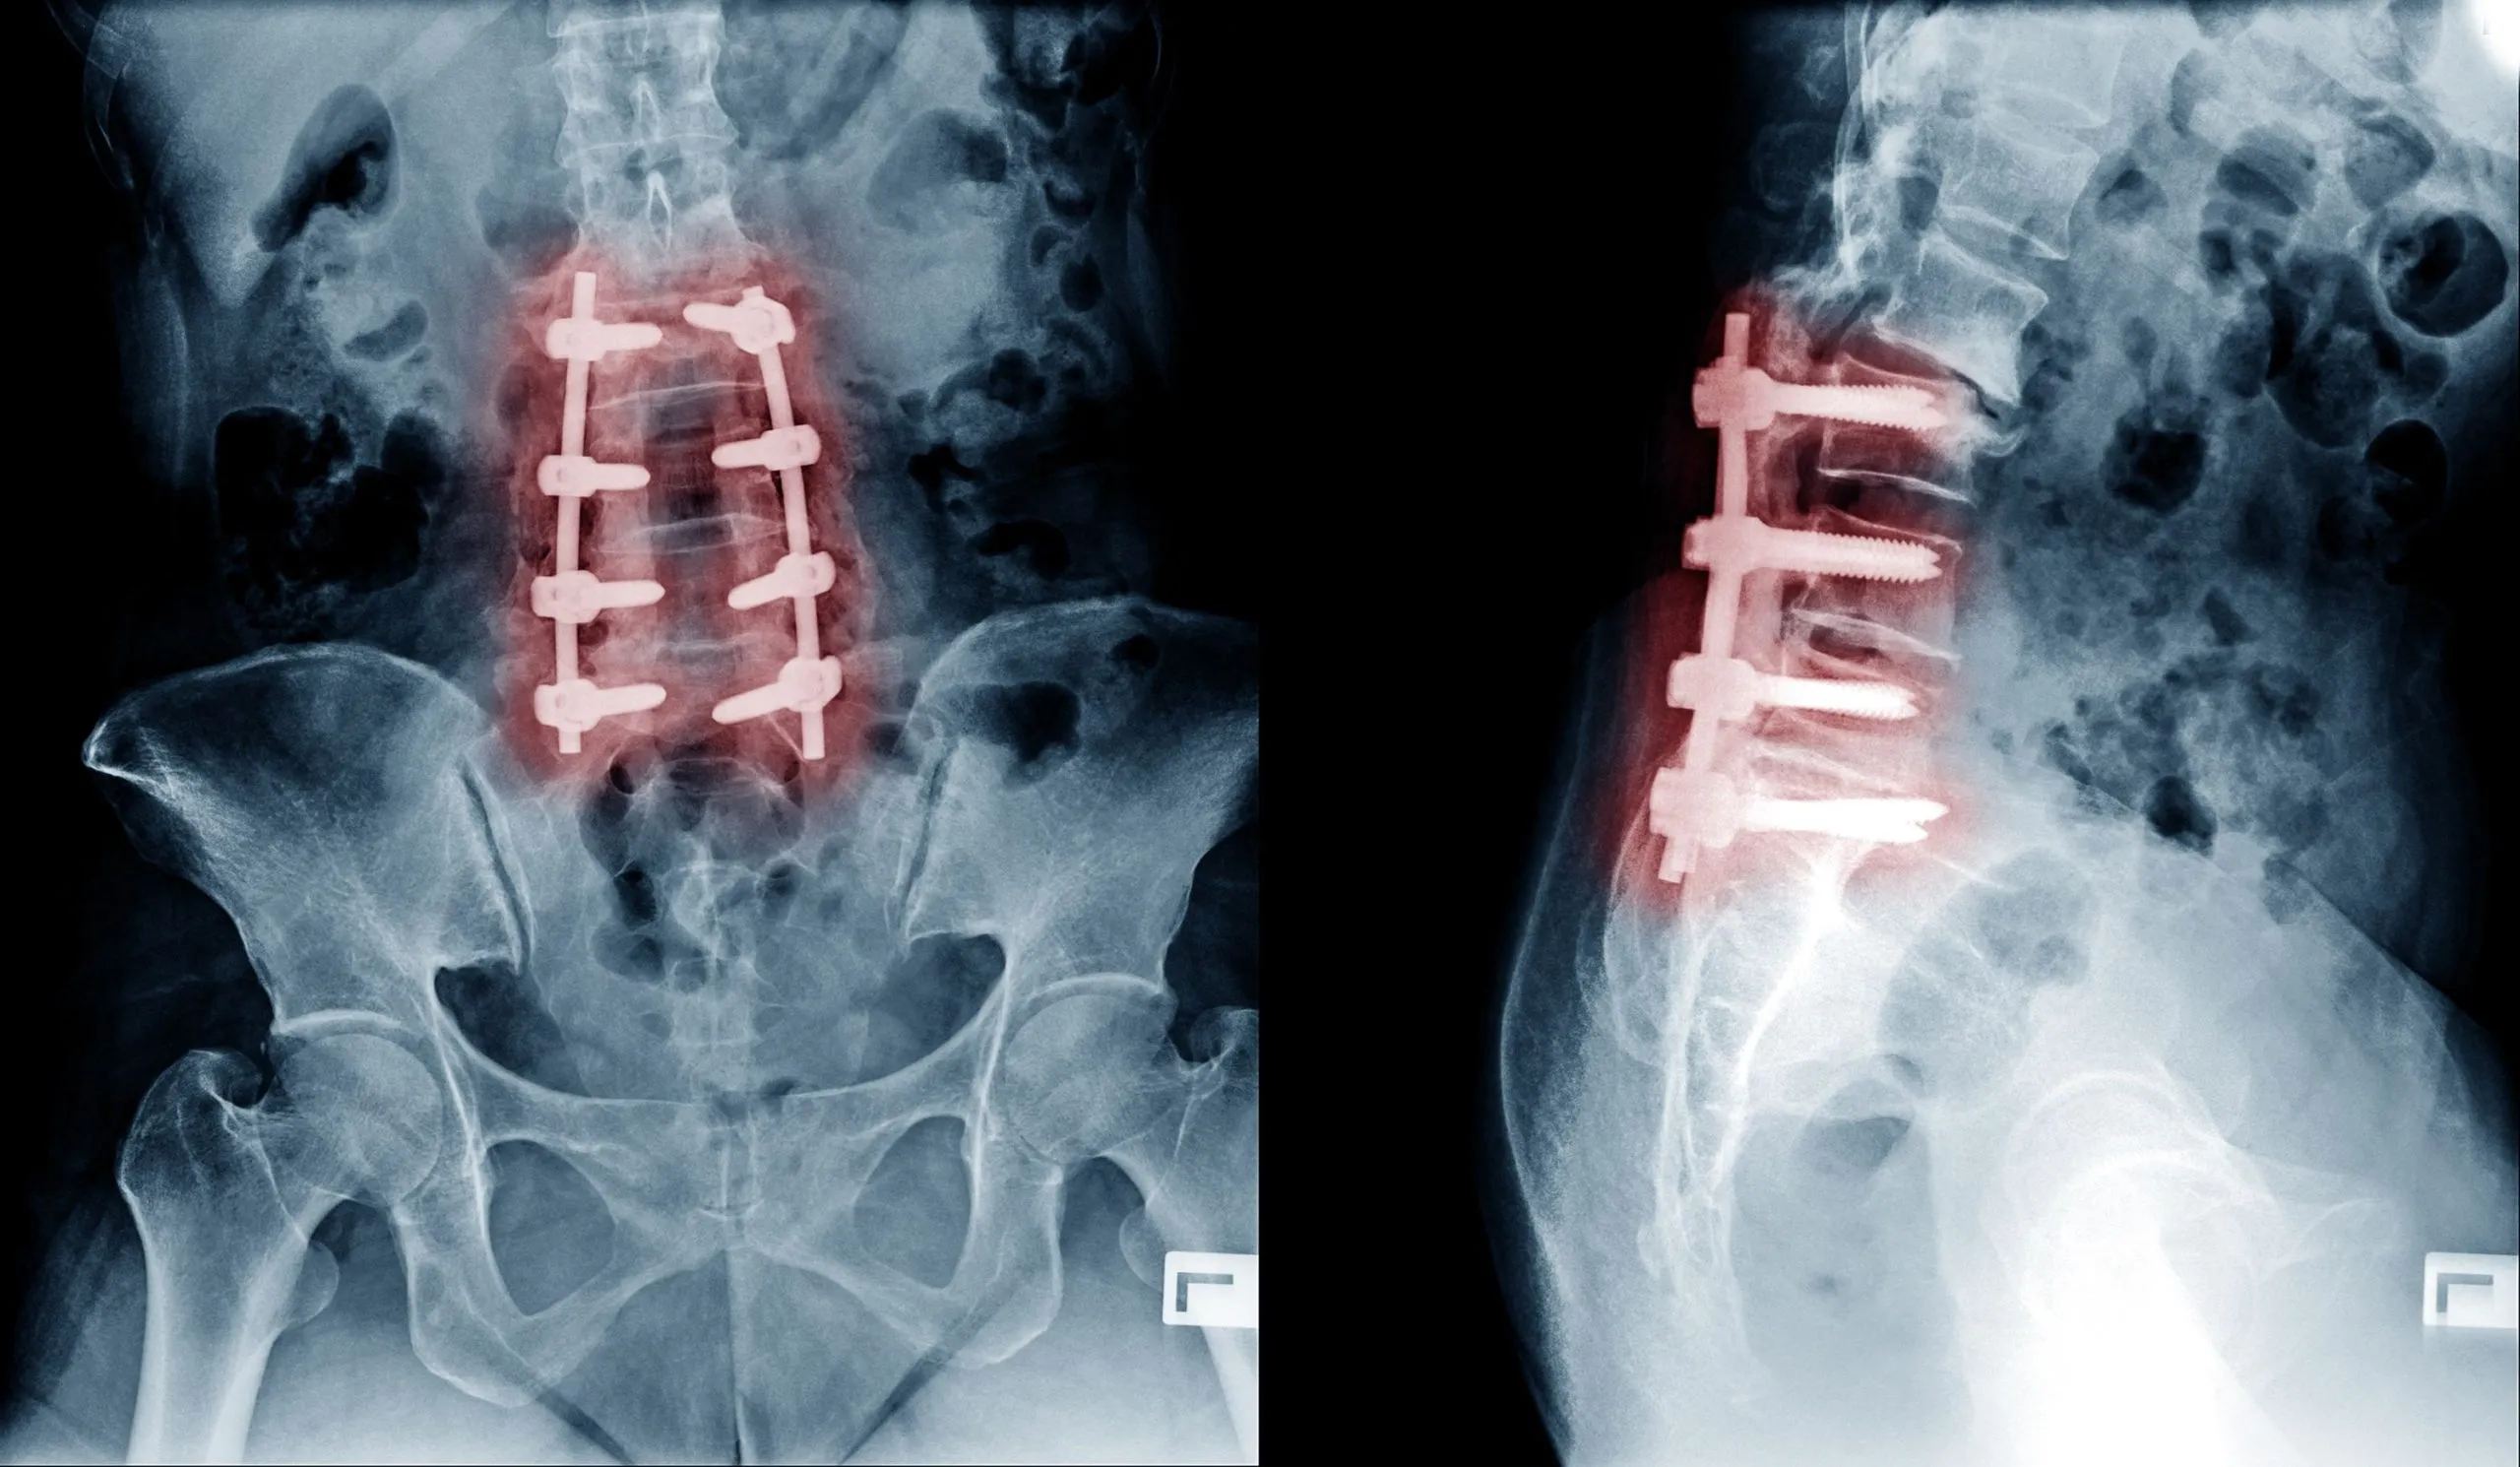

Surgical complications. Complications of spinal fusion occur in up to 18% of patients, ranging from infection and blood clots to stroke, pneumonia, heart and lung problems, and death. 1

Hardware failure. Screws loosen, rods break, cages migrate. Each hardware problem typically requires another operation.

Pseudarthrosis. The bone graft fails to fuse in a meaningful percentage of cases, leaving the patient with hardware, motion at a level that was supposed to be locked, and pain.

The procedure is performed through a 4mm to 7mm incision. There is no muscle cutting, no bone removal, no hardware, and no fusion. A precision laser is used to remove the herniated disc material and decompress the inflamed annular tear that is generating the pain. Because nothing is fused and nothing is implanted, there is no adjacent segment disease, no pseudarthrosis, no hardware failure, no post-operative narcotics, and no months-long recovery.